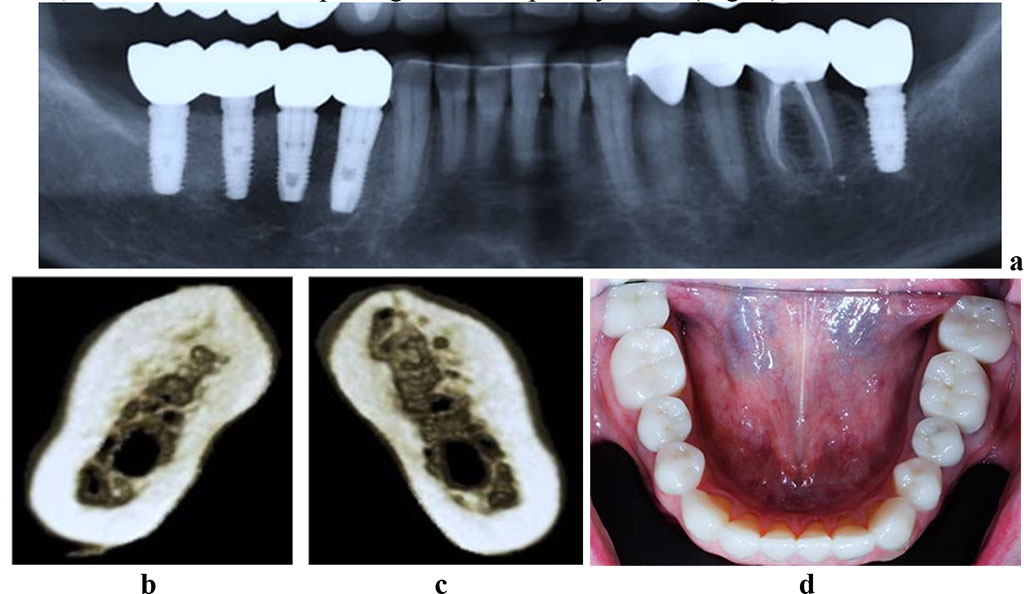

The CBCT of the cross-sectional 3D window at the area of planned dental implantation in the main group revealed minor changes in the bone tissue microarchitectonics, while the amount of bone was maintained. The 3D window of volumetric rendering mode showed that at the area of dentition defects, the cortical bone was wide and intact throughout. There were some minor qualitative changes observed in the spongy bone: the spongy bone trabeculae width and the bone trabeculae structure density were slightly reduced; there were some spots identified where the intertrabecular space was expanded; the vestibular and lingual cortical plates were intact; the trabecular structure preserved its integrity yet there was a slight change in the structure arrangement (disorientation) observed in the bone trabeculae (Fig. 6-8).

Figure 6. Patient K., 57 y.o. Diagnosis: lower jaw partial adentia; Class I by Kennedy. Lower jaw CBCT: a – bone tissue 12 months following the installation of dental implants (panoramic reformat); 3D cross-sections at the adentia area 3.6 (b) and 4.6 (c) prior to the installation of dental implants; d – lower dentition after implantological and prosthetic treatment.